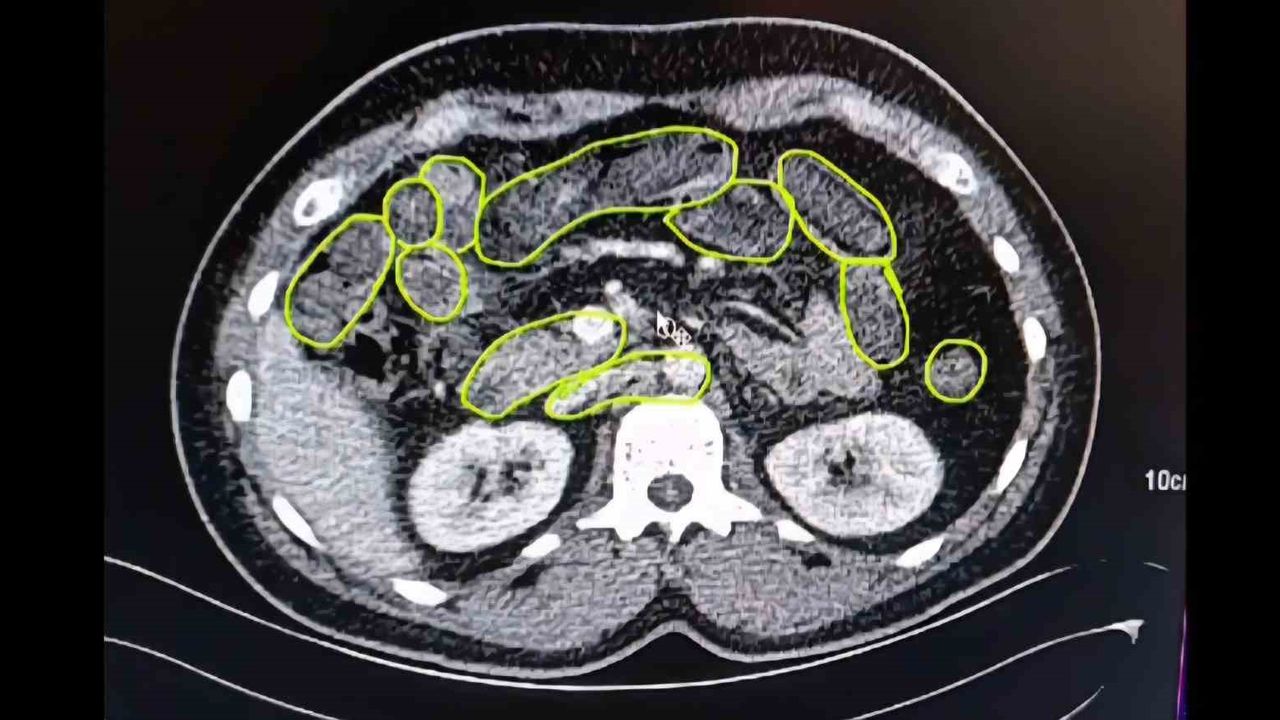

Şüphelilerin Kayseri Şehir Hastanesinde iç beden muayenesine alınırken, mide ve bağırsaklarında da çok miktarda kapsül şeklinde uyuşturucu olduğu değerlendirilen yabancı maddeler tespit edildi.